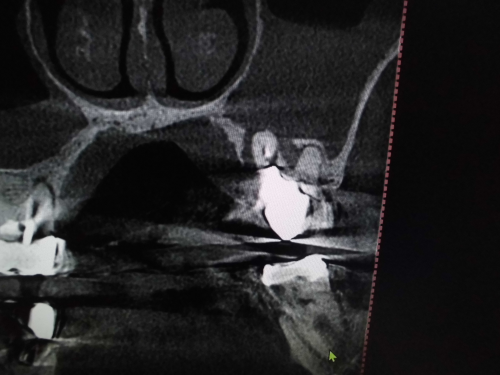

左上奥歯が割れています。一般的なレントゲンではわかりません。

CTでは破折線がはっきり見えます。患者様も納得しやすいです。